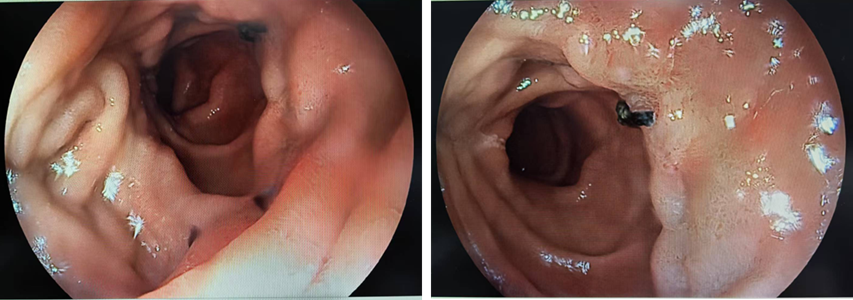

胃镜检查:十二指肠降段外侧壁见一平坦隆起病变,边界清晰,色泽发红ME - NBI 下可见不规则 MS,呈villi改变,可见WOS(白色不透光物质)附着。考虑十二指肠降段早期癌。

image.png

图1 胃镜检查结果